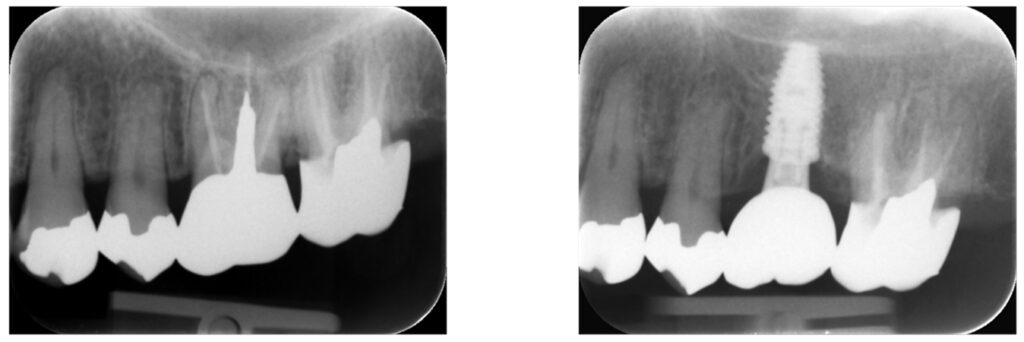

症例40:歯根破折している歯の抜歯とインプラント治療

歯根破折している歯の抜歯、インプラント治療をする。

痛みや腫れの除去しっかり噛める咬合関係の確立。